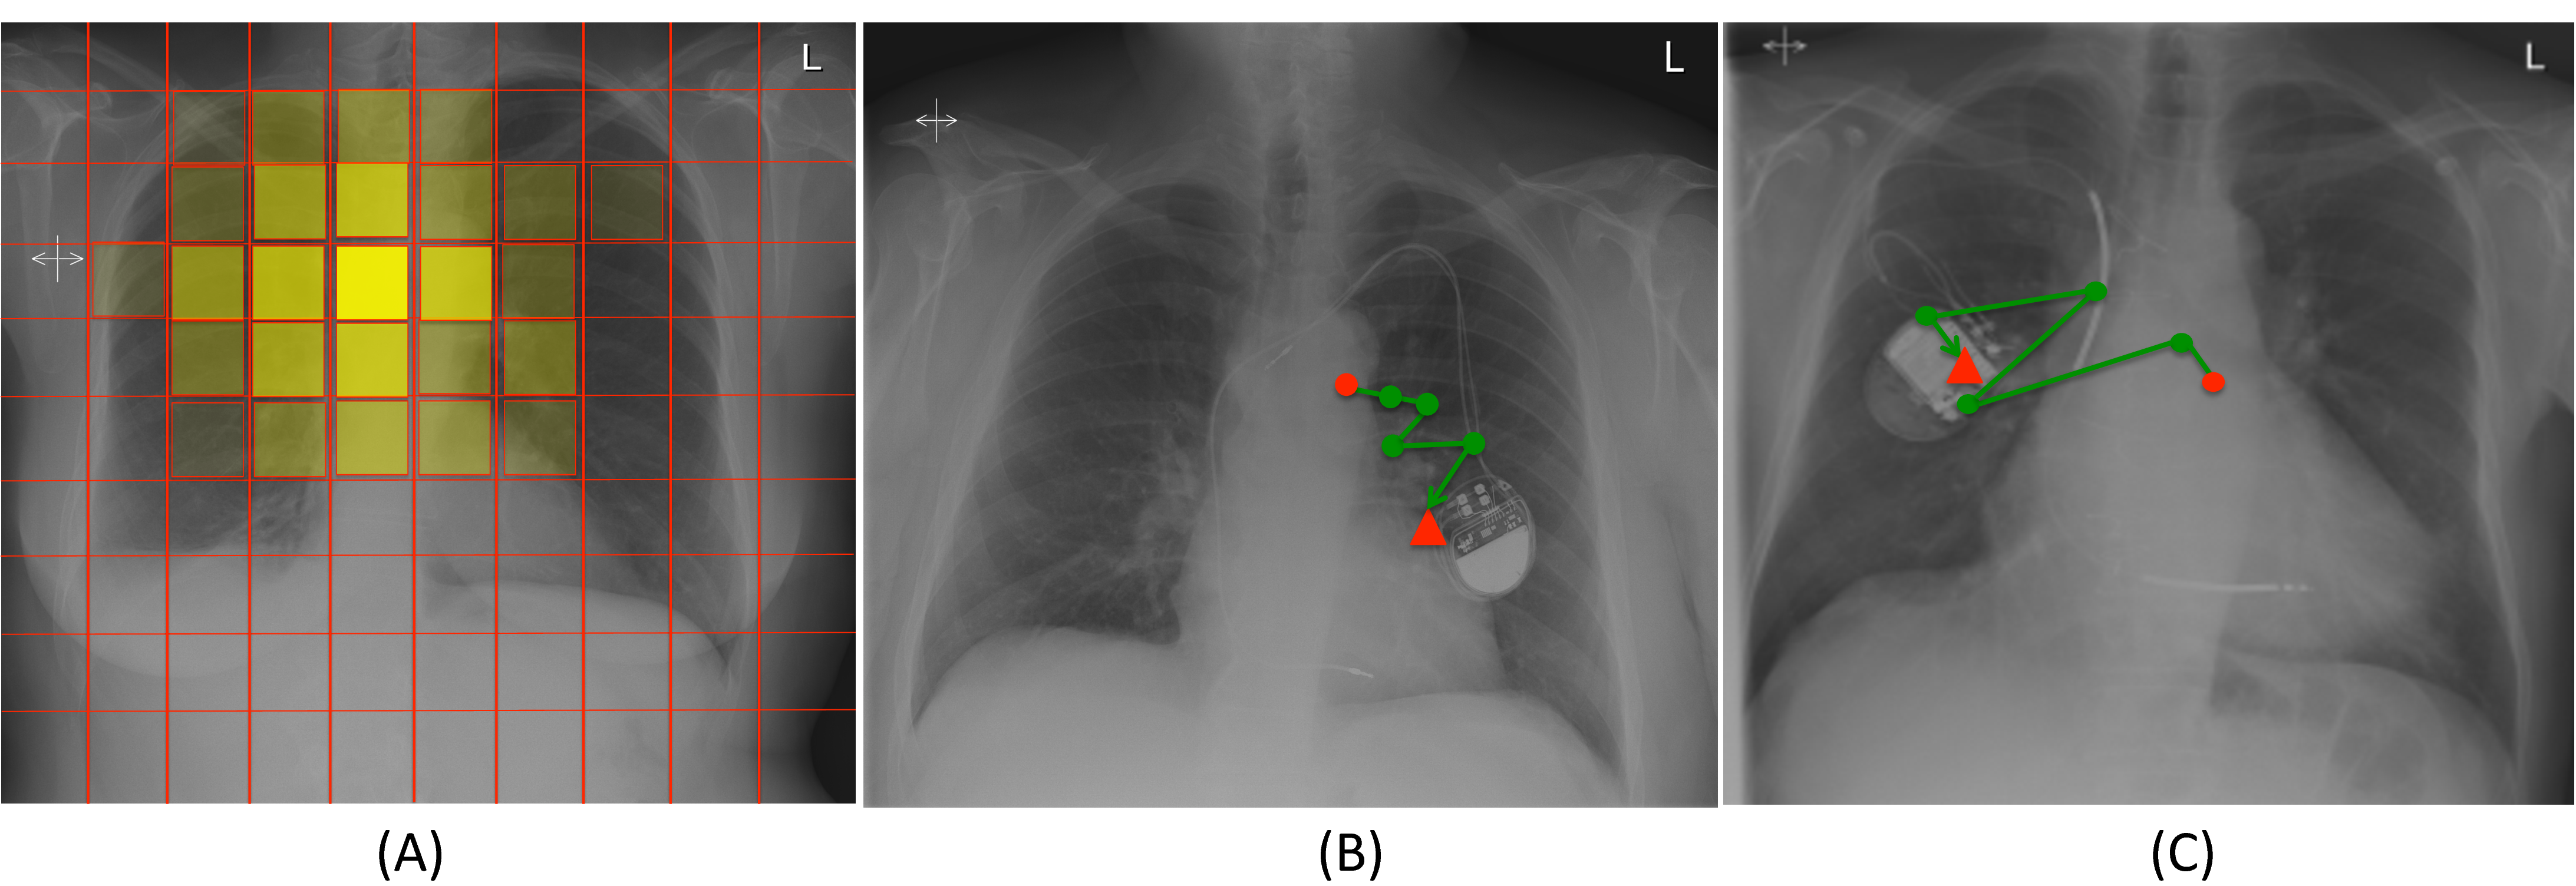

Analogously, Figure 4 (A) highlights frequently explored locations when trying to discriminate between normal and enlarged hearts. Here it can be observed how the models learns to focus on the cardiac area. Two samples of the learned policy are illustrated in Figure 4 (B), (C). The trajectories followed here demonstrates how the policy has learned that exploring the extremities of the heart is required in order to conclude whether the heart is enlarged or not.

Figure 4: (A) Image locations attended by the RAM model for the detection of enlarged hearts. (B) and (C) are two different samples of the learnt policy on test images.